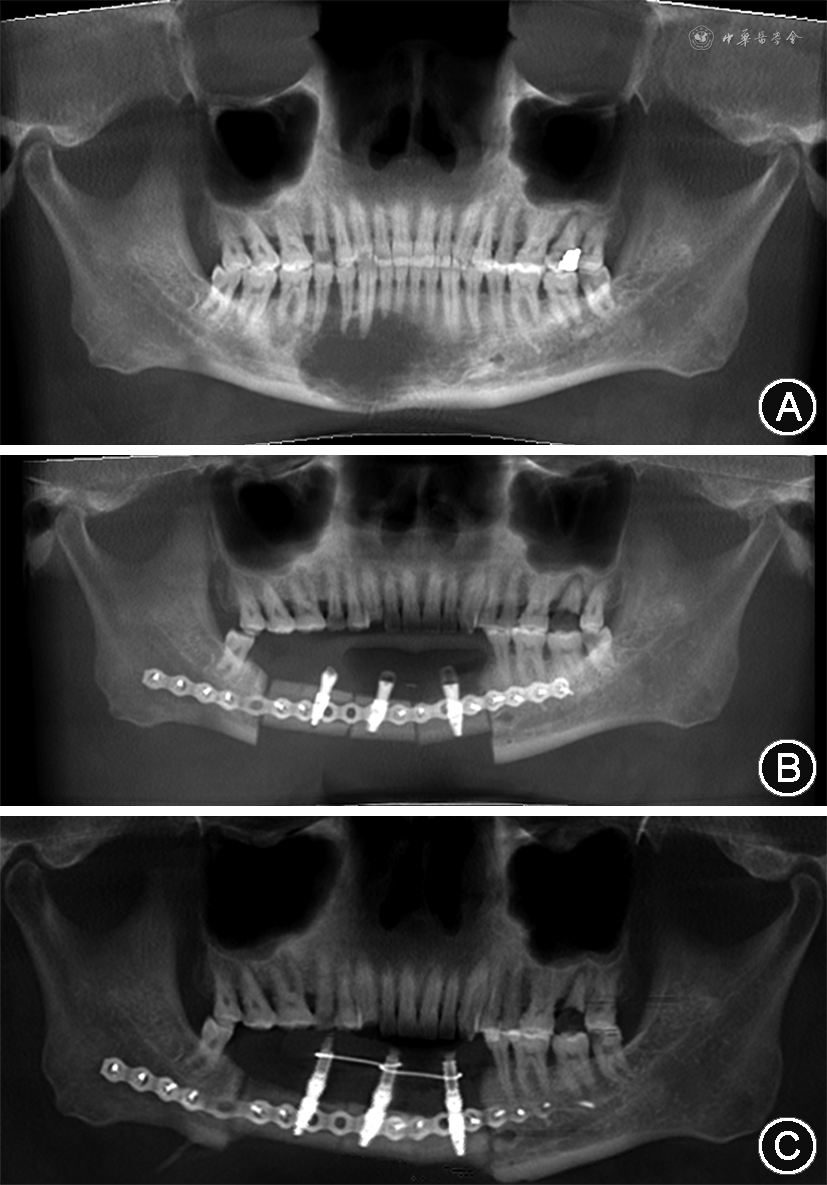

2. 检查:见图1,2。患者右侧面下份和右下颌前庭沟较左侧稍膨隆,表面皮肤无异常;下颌牙列无明显松动;41—43唇侧前庭沟见未愈合切口,缝线在位无松脱,唇侧轻微触压痛,舌侧无明显异常。锥形束CT显示,下颌骨46—32区域大范围不规则骨质破坏区,边界不清,其内密度均匀,牙根无吸收(图2A)。